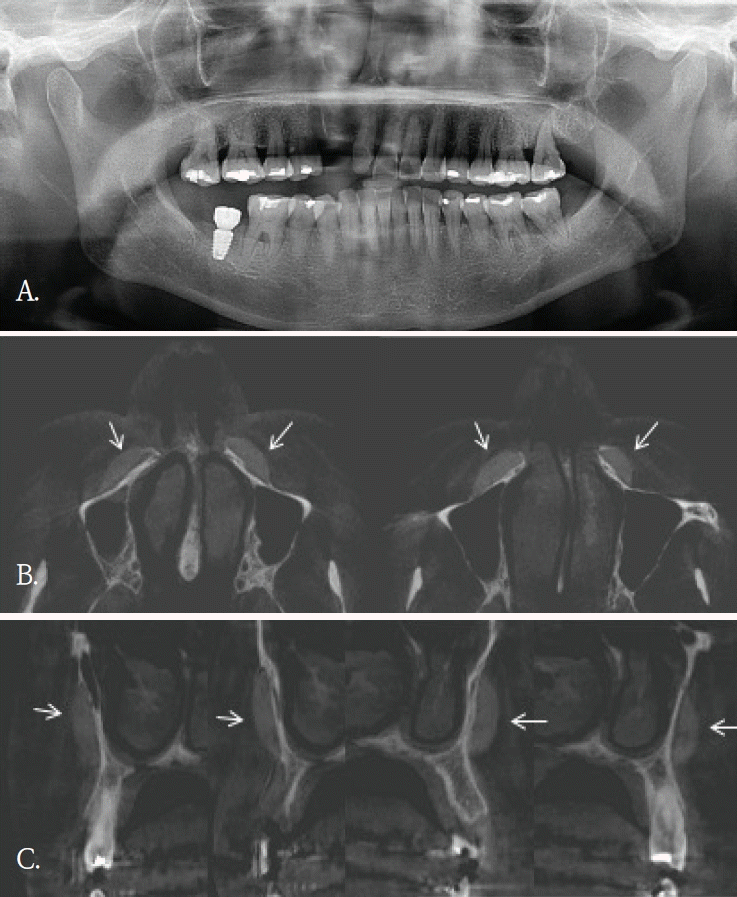

Fig. 1.

A. Panoramic radiograph shows no definite abnormality in the maxillary anterior region. B. Cross-sectional cone-beam computed tomographic image of the maxillary anterior alveolar region demonstrates a small block-shaped radiopaque foreign body in the labial soft tissue, without intraosseous involvement.

20대 여자환자가 윗 입술의 불편감을 주소로 내원하였다. 파노라마방사선영상에서 관련된 이상소견이나 병변이 관찰되지 않았다(Fig. 1A). 과거병력 청취에서 교통사고로 인한 윗 입술 열상의 봉합 병력이 있었음을 파악한 후, 외상 후 연조직 섬유화로 진단되었다. 1년 후, 이물감을 호소하면서 환자는 재내원하였다. 파노라마방사선영상에서는 여전히 이상소견이 관찰되지 않았기에, 콘빔CT검사를 시행하였다. 윗입술과 상악 전치사이 연조직부위에서 블럭모양의 방사선불투과성 이물질이 발견되었다(Fig. 1B). 이물질 제거를 위한 외과적 수술이 시행되었고, 술 후 해당 이물질은 유리조각임이 확인되었다.- 증례 2

콘빔CT는 해부학적 구조물이나 이물질 위치를 확인하고, 인접 구조물과의 관계를 파악하는데 유리하다. 2차원 영상에서 발생되는 중첩을 줄이고, 3차원적인 위치정보를 제공함으로써 치과 임플란트 치료계획이나 치아 교정 진단과정에서 필수적인 영상검사이다. 또한, 임플란트 식립이나 매복치 발거등 외과적 치료과정에서도 진입 경로 결정에 도움을 주어 술 후 합병증을 감소시킨다.콘빔CT의 원래 촬영 목적과는 관계없이, 우연히 발견되는 소견들이 있다. 이러한 소견의 빈도는 24.6~94.3%로 보고마다 매우 다양하다[1,2]. 소아 및 청소년연령군에서의 빈도도 0.4~80.3%로 다양하지만 매우 자주 발견된다[3]. 발견되는 부위는 치아 및 치조골을 벗어난 부위가 대부분으로 주로 부비동 및 비강, 혈관, 연조직, 경추이다[1-3]. 그러므로, 콘빔CT 검사할 때 촬영목적 부위 뿐 만 아니라 그 외 다른 부위의 판독도 충분히 이루어져야 한다[2,4,8]. 특히 어린 환자에서는 방사선방어를 고려하여, 관심부위 뿐 만 아니라 콘빔CT영상에 포함된 모든 부위에서 영상판독이 충분히 이루어져야 한다[3]. 우연히 발견되는 소견의 양상도 매우 다양하다. 부비동 및 비강에서는 점막비후, 점액저류낭, 비중격만곡이 많이 발견되고, 혈관부위에서는 경동맥석회화가 주로 발견된다. 연조직에서는 편도석, 경동설골인대골화가 주로 발견되는 소견이다[1-3]. 대부분 해부학적 변이이거나 의학적 조치가 필요하지 않은 경우이다.하지만 추적검사나 치료가 필요한 임상적으로 의미가 있는 소견들도 매우 다양한 빈도로 발견된다. 최소 0.4%에서 최대 37%까지로 전체의 약 1/6-1/3 정도에서 발견되어 주의깊은 콘빔CT 영상판독이 필요하다. 이들 소견중에는 치근단병소, 치성낭, 종양도 있었으며[1-3], 오랜 기간 동안 인지하지 못했던 이물질도 발견된다[1,4,6,8].우연히 발견된 이물질들은 치조골 및 악골 부위가 아닌 다른 부위에서 많이 관찰되었다. 교정목적으로 촬영된 콘빔CT에서 비강내에 플라스틱 이물질이 우연히 발견되어 이비인후과 의뢰 후 이물질을 제거한 증례보고가 있다[4]. 증상이 없어서 이물질의 유무를 알 수 없었지만, 콘빔CT에서 비강내 이물질이 확인되어 외과적으로 제거한 증례보고도 있다[5,6]. 증상이 있어 촬영한 상악 견치 치근단방사선사진에서 모호한 방사선불투과성 이물질이 관찰되어, 이후 촬영한 콘빔CT에서 이물질이 유리조각으로 확인된 증례보고도 있다[8]. 이 증례는 유리같은 이물질은 치근단이나 파노라마방사선사진에서는 명확하게 관찰되지 않았기에 콘빔CT검사가 매우 유용하였던 경우이다.증례 1에서도 초진시 파노라마영상에서는 유리조각을 관찰할 수 없었기에 연조직 병변으로 진단되었으나, 재내원후 촬영된 콘빔CT영상에서 연조직내에 있었던 이물질임으로 확인된 경우이다. 윗입술에 있었던 유리조각이 방사선불투과성 물질이였지만, 상악 전치부와 중첩되어 파노라마방사선영상에서 뚜렷하게 구분되지 않았다.증례 5와 같이 파노라마방사선영상에서 모호하게 관찰되었거나 증례 3과 4같이 파노라마방사선영상에서 협-설위치를 명확하게 알 수 없었던 경우, 콘빔CT영상에서 임상적으로 의미있는 이물질임을 확인되었고 외과적 치료가 시행되었던 증례들이다. 특히, 이들 소견은 악골이 아닌 안면 연조직 부위에서 관찰되어, 주의 깊은 영상판독의 중요성을 다시금 일깨워 준다.한편, 안면미용시술을 받은 환자들이 치과에 많이 내원하면서 우연히 발견되는 이물질 소견 중 하나가 미용 필러이다[9]. 치과의사들에게 아직은 익숙하지 않은 방사선영상 소견이고 부위도 치아나 악골이 아닌 연조직부위에서 관찰되기에 영상 판독에서 배제될 가능성이 있다. 미용필러도 파노라마방사선 영상에서보다는 콘빔CT영상에서 위치나 형태, 양상을 잘 관찰할 수 있다.본 증례들은 파노라마방사선영상에서 인지되지 않았던 이물질 3증례와 파노라마방사선영상에서 의심된 이물질이 콘빔 CT에서 위치와 형태가 명확히 규명된 2증례를 포함한다. 이를 통해 악안면 콘빔CT 판독 시 촬영 목적 부위에 국한하지 않고 영상에 포함된 전체 영역을 체계적으로 검토함으로써, 이물질과 같은 우연히 발견되는 소견이 누락되는 것을 줄일 수 있음을 알았다. 또한 추가 촬영이나 불필요한 검사로 인한 방사선 노출을 예방하여, 콘빔CT 검사의 정당성과 임상적 유효성을 강화하는 뒷받침이 됨을 알았다.